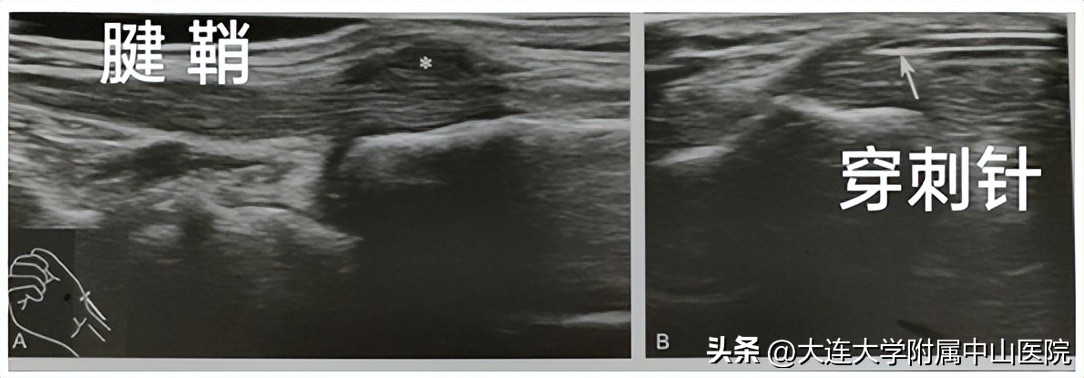

1.超声引导下狭窄性腱鞘炎(“妈妈手、扳机指”)的松解及药物治疗